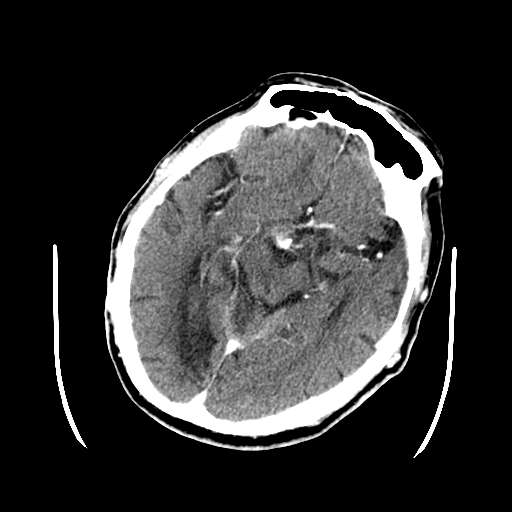

多发性脑梗塞肯定存在,请问版主,病灶是否有强化?定位应在脑外病变,脑膜瘤?动脉瘤?

皮脑应该可以诊断,不知道增强病灶有没有强化(ct值),从片上看好像有轻度强化,定位像是脑外的,圆形高密度,内部有点状更高密度考虑为点状钙化,首先考虑为脑膜瘤.鉴别诊断:胶质瘤,垂体瘤,听神经瘤等.

这次病变主要是是因为脑干及小脑的梗塞,另外原有多发脑梗塞。右侧鞍上池及颞叶区可见一大部钙化的病灶,强化后略有增大,并见一条血管进入,考虑血管瘤。不排除脑膜瘤可能!~!

无占位,无水肿带,大部分钙化,av畸形?增强的图片都不尽量在同层面,难比较强化,如果有强化迹象肯定是av畸形!